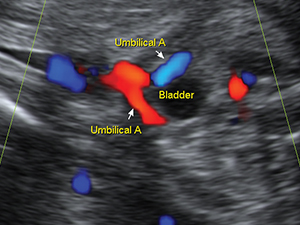

Fetal bladder